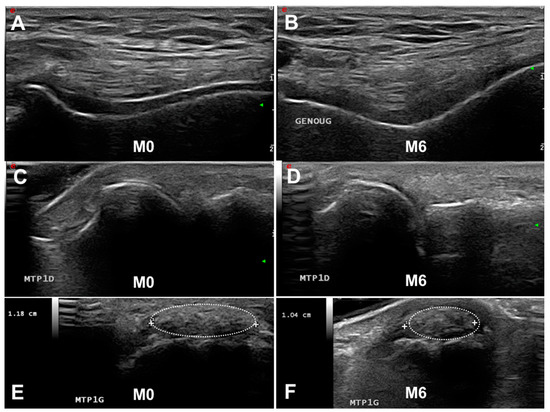

- Double contour sign: “abnormal hyperechoic band over the superficial margin of the anechoic cartilage, independent of the angle of insonation and which may be irregular, continuous, or intermittent and can distinguished from the cartilage interface sign” (Figure 1A,C). The DC sign must be searched preferentially at the first metatarsophalangeal joints (MTP1s), the trochleal cartilage of knees (suprapatellar plane in maximal flexion) and the talar cartilage.

- Tophus: “a circumscribed, inhomogenous, hyperechoic and/or hypoechoic aggregation (which may or may not generate a posterior acoustic shadow)” (Figure 1E,F). The main locations for detecting US tophus are the MTP1s and quadricipital and patellar tendons.